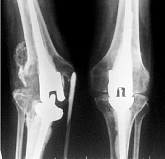

Endoprothetik des Kniegelenks

In den späten Stadien der Arthrose des Knies durch eine ausgeprägte Begrenzung der Bewegung begleitet, konstant starke Schmerzen, körperliche Unversehrtheit Verformung bis zur Genesung der einzige Weg ist der Ersatz des betroffenen Gelenks für eine künstliche - Endoprothetik.

Diese Methode ermöglicht es Ihnen, die richtige Form des Gliedes, eine vollständige Palette von Bewegung im Gelenke, zu entlasten ständige Schmerzen und Knirschen bei Bewegung und als Ergebnis wieder herzustellen, signifikant dem Patienten Lebensqualität zu verbessern.

Im Folgenden sind Röntgenaufnahmen und Fotografien, die die Strecke der Bewegung in der betroffenen Gelenke vor und nach der Operation veranschaulichen.